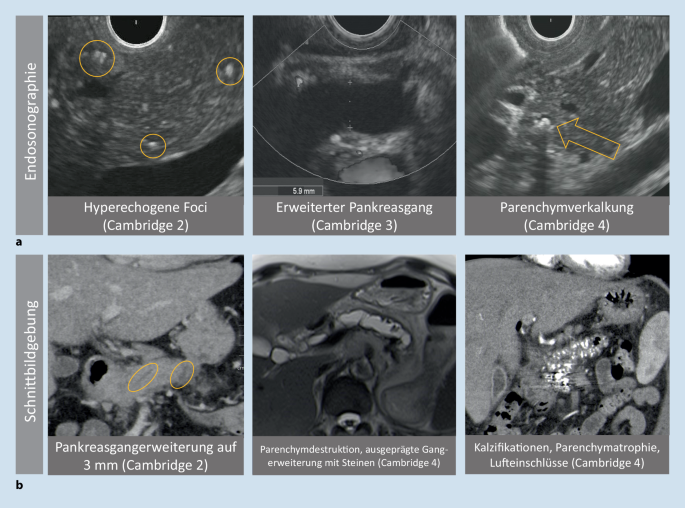

Endosonographie (EUS): Der hochauflösende Blick von innen

Die Endosonographie (EUS) gilt als die sensitivste Methode zur Erkennung früher morphologischer Veränderungen der Bauchspeicheldrüse. Dabei wird ein Ultraschallkopf über ein Endoskop eingeführt, was eine sehr detailreiche Darstellung des Pankreas und seiner Gänge ermöglicht. Zur standardisierten Beurteilung der Befunde werden häufig die sogenannten Rosemont-Kriterien herangezogen. Ein weiterer Vorteil der EUS ist die Möglichkeit, gezielt Gewebeproben (Biopsien) aus auffälligen Bereichen zu entnehmen oder Flüssigkeiten aus Zysten zu punktieren.

Computertomographie (CT): Wann sie unverzichtbar ist und was sie zeigt

Die Computertomographie (CT) ist ein weiteres wichtiges bildgebendes Verfahren, das in der Diagnostik der chronischen Pankreatitis eine Rolle spielt. Sie eignet sich hervorragend zur Darstellung von Verkalkungen, die ein typisches Zeichen der chronischen Entzündung sind, sowie zur Detektion von Pseudozysten und zur Beurteilung von Komplikationen. Zudem ist die CT sehr nützlich, um andere Erkrankungen im Bauchraum auszuschließen, die ähnliche Symptome verursachen könnten. Allerdings ist zu beachten, dass die CT mit einer Strahlenbelastung verbunden ist.